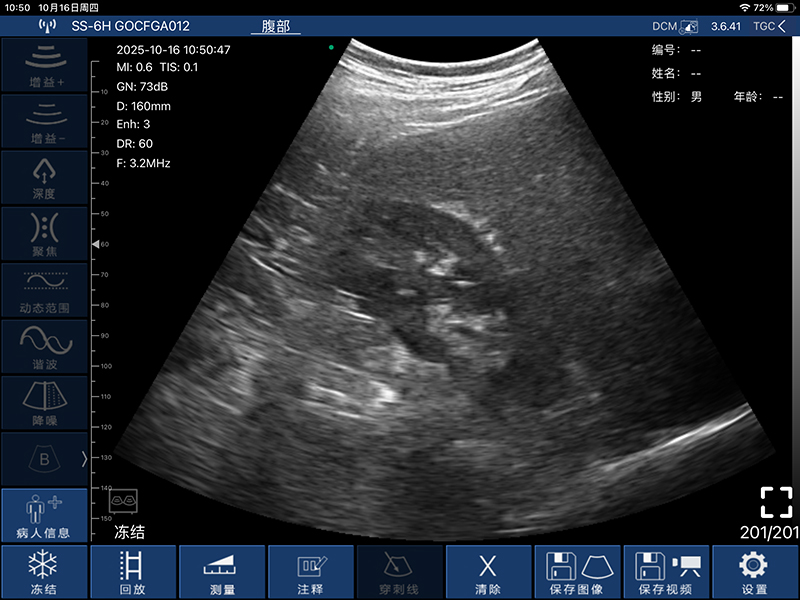

• 扫描方式:电子阵列扫描

• 探头频率:3.2/5.0MHz

• 增益30db-105db

• 扫描深度:90/160/220/305mm,可调

• 显示模式:B、B/M、Color、PW、PDI

• 图像调节:增益、焦点、反相脉冲谐波、降噪